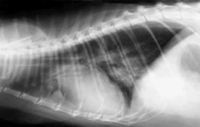

Рентген грудной клетки. Рентгеновский снимок выполняют в двух проекциях – когда животное находится в положении лежа на боку и лежа на животе.